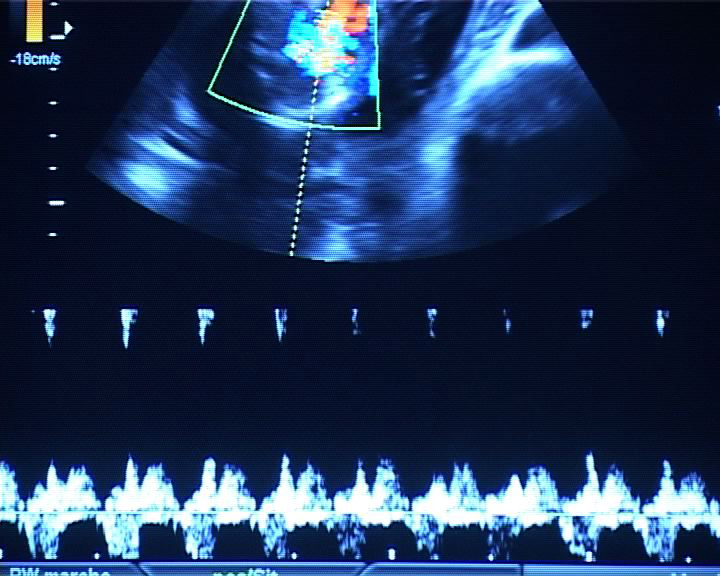

The filmmaker's point of view on what midwives experience today (she was herself a midwife for 5 years). An attempt to make the audience feel what they, the women, and even what the fœtuses, feel. A mixture, at times a fight, between the women’s wish - their right - to give birth in “this secret ceremony” where the sacred is not out of place, and the context of the highly technological environment which “accompanies” delivery, maternity and giving birth today.